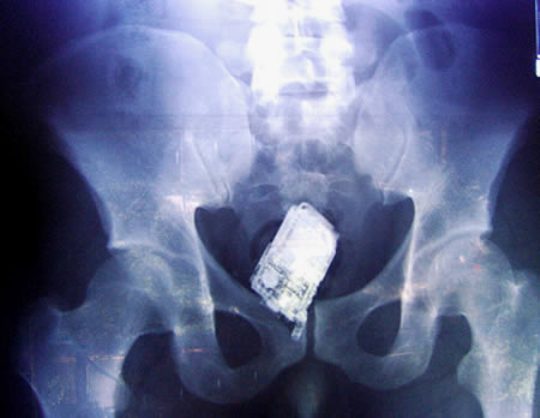

Possible old-school cell phone?

phone